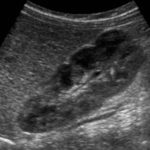

3-Duplex kidney

هذا مصطلح واسع يشمل عدة متغيرات منها وجود كليتين ملتصقات ببعض أو وجود two collecting systems في كلية واحدة. وهذه أيضا يوجد بها متغيرات أخرى من ناحية وجود حالب واحد أو حالبين ووجود شريان واحد أو اثنين.

يوجد هذا المتغير في قرابة ١٠٪ من الناس الطبيعيين. ويجب على الأخصائي التأكد من عدم توسع الحالبين وأيضا عدم وجود انسداد في أحد collecting systems وتحديدا العلوي.